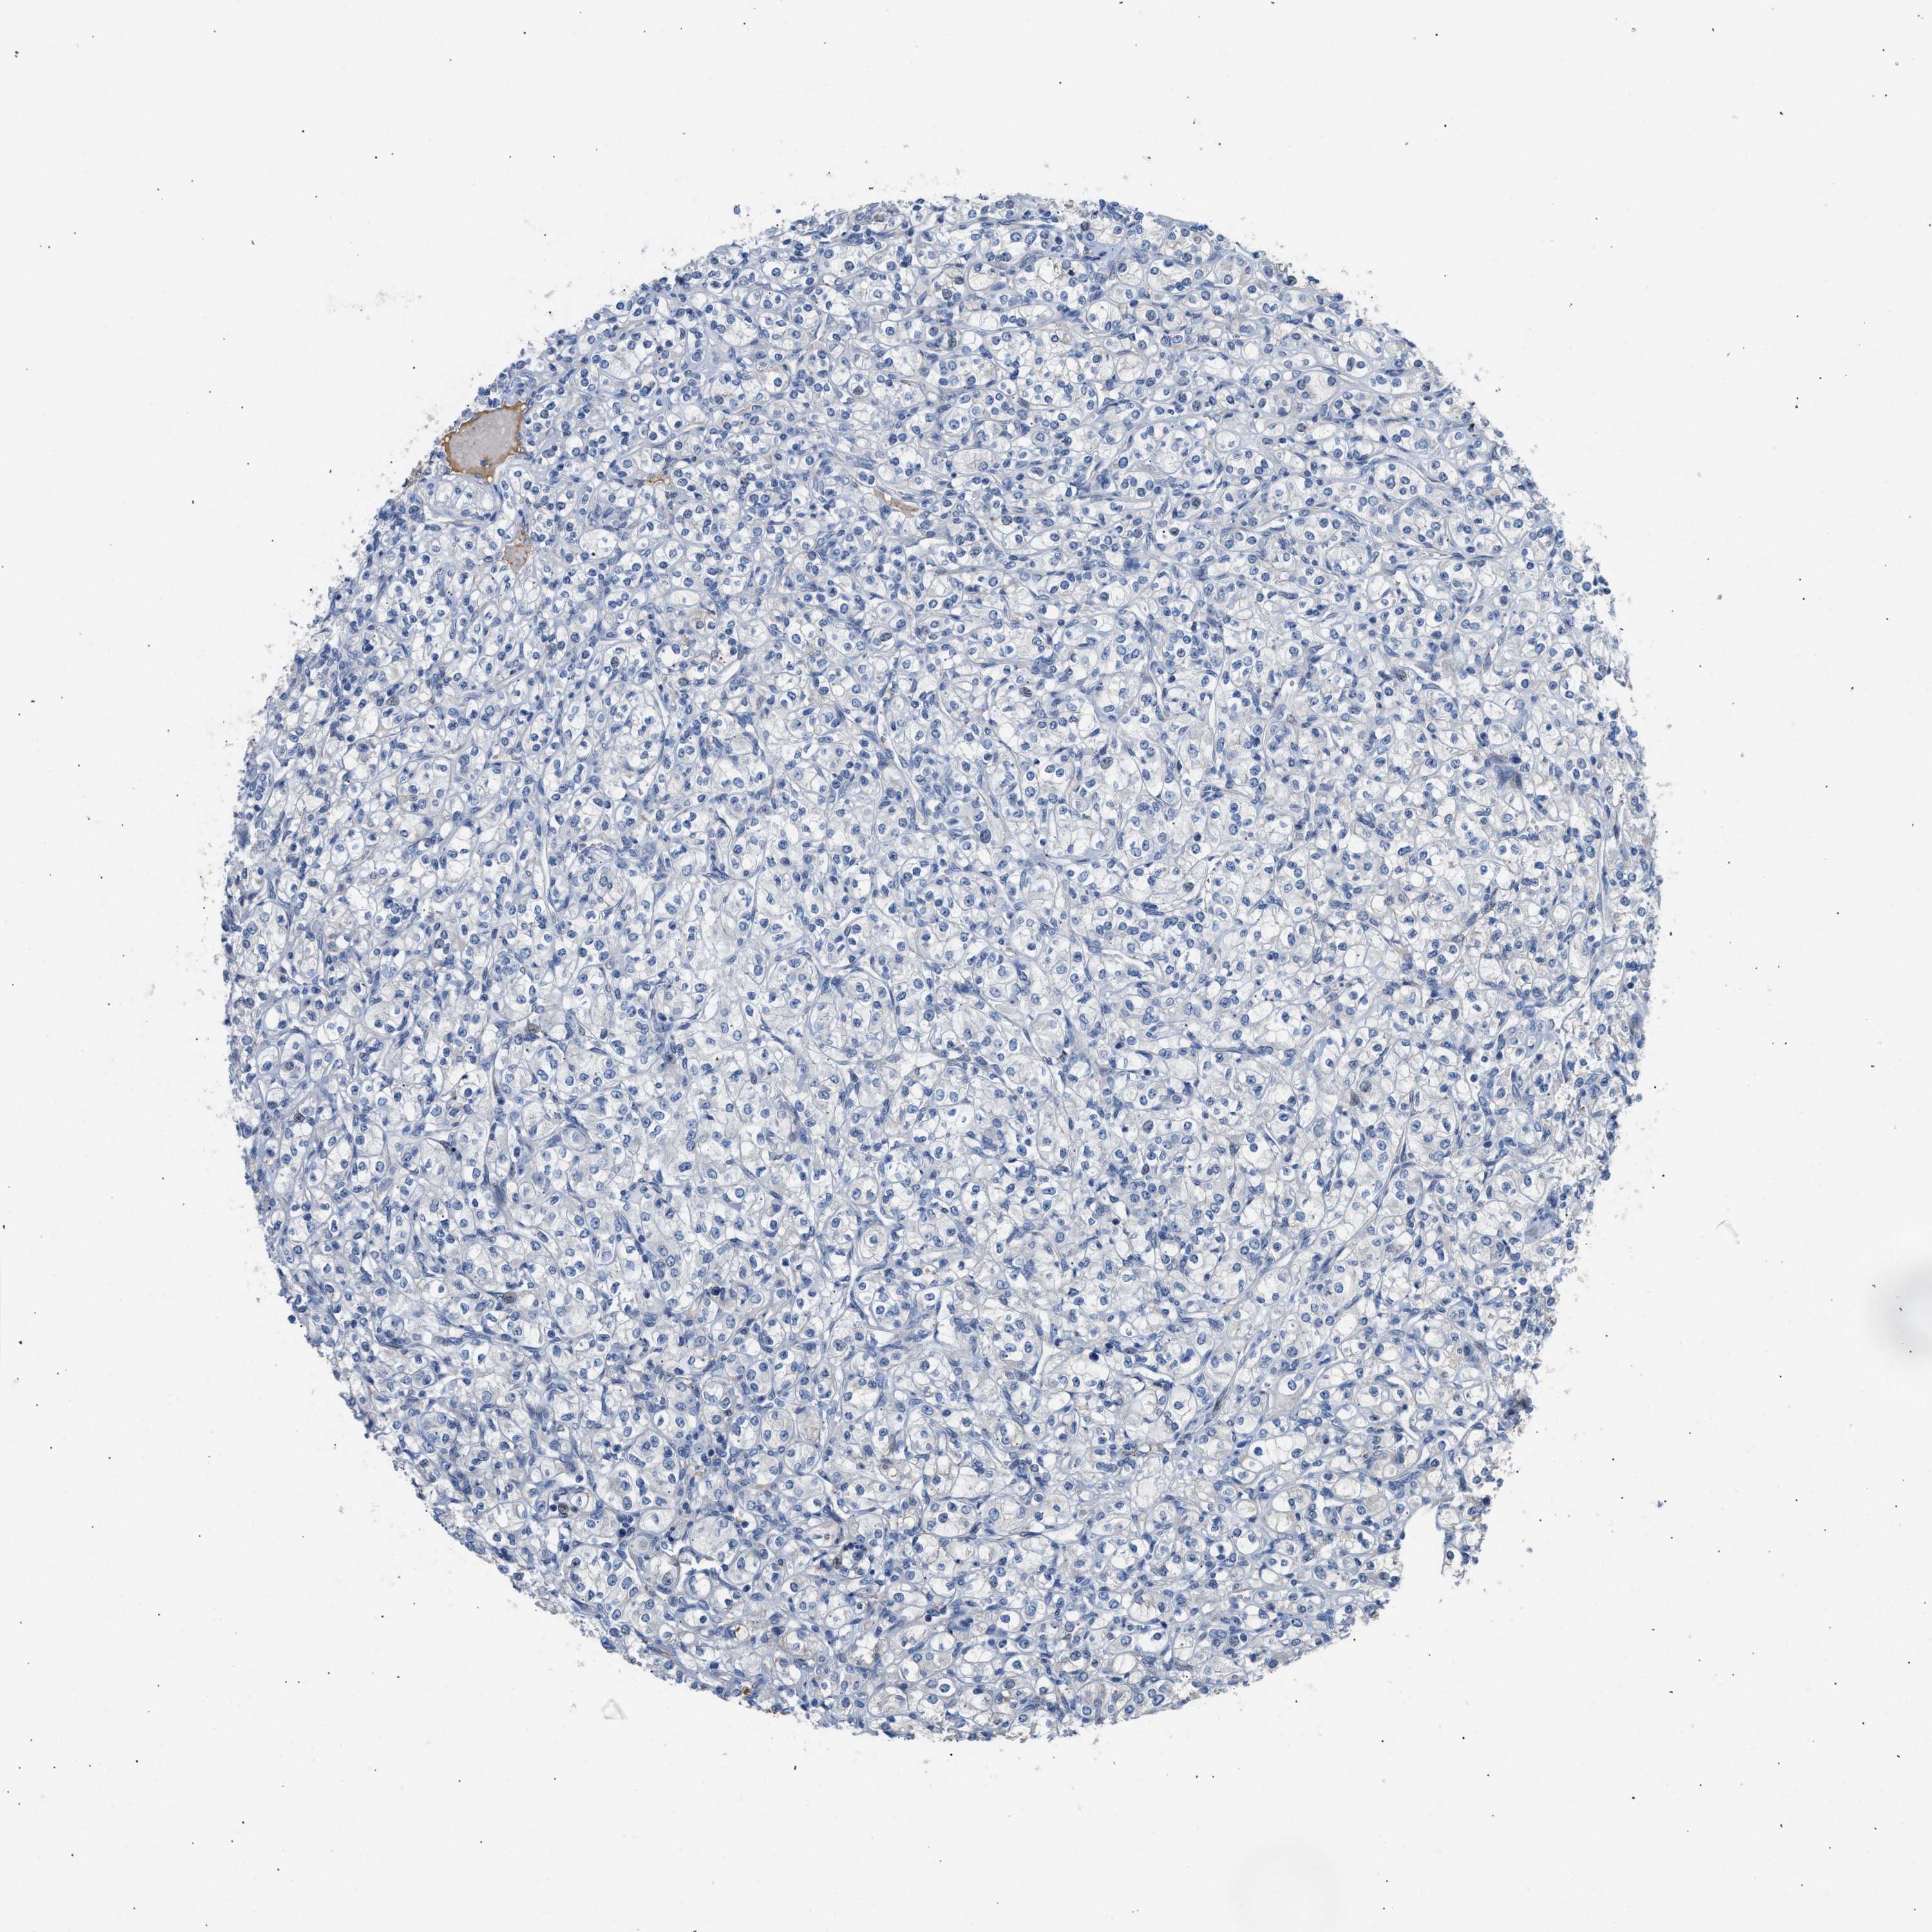

KIDNEY RENAL PAPILLARY CELL CARCINOMA (TCGA) - Interactive survival scatter ploti

The Survival Scatter plot shows the clinical status (i.e. dead or alive) for all individuals in the patient cohort, based on the same data that underlies the corresponding Kaplan-Meier plots. Patients that are alive at last time for follow-up are shown in blue and patients who have died during the study are shown in red.

The x-axis shows the expression levels (FPKM) of the investigated gene in the tumor tissue at the time of diagnosis. The y-axis shows the follow-up time after diagnosis (years). Both axes are complimented with kernel density curves demonstrating the data density over the axes. The top density plot shows the expression levels (FPKM) distribution among dead (red) and alive patients (blue). The right density plot shows the data density of the survived years of dead patients with high and low expression levels respectively, stratified using the cutoff indicated by the vertical dashed line through the Survival Scatter plot. This cutoff is automatically defined based on the FPKM cutoff that minimizes the p-score. The cutoff can be changed by dragging the vertical line or by entering a cutoff value in the square labeled "Current cut-off".

Under the Survival Scatter plot the p-score landscape (black curve; left axis) is shown together with dead median separation (red curve; right axis). Dead median separation is the difference in median mRNA expression between patients who have died with high and low expression, respectively. It is calculated as follows: median FPKM expression of dead patients with high expression - median FPKM expression of dead patients with low expression. This is intended to aid the user in visually exploring custom cutoffs and the associated p-scores and dead median separation.

Individual patient data is displayed and can be filtered by clicking on one or more of the category buttons on the top of the page. Categories describing expression level and patient information include: high, low, alive, dead, female, male and tumor stages. The scale of the x-axis can be toggled between linear and log-scale by clicking on the "x log" button. Mouse-over function shows TCGA ID, patient information and mRNA expression (FPKM) for each patient.

& Survival analysisi

Kaplan-Meier plots summarize results from analysis of correlation between mRNA expression level and patient survival. Patients were divided based on level of expression into one of the two groups "low" (under cut off) or "high" (over cut off). X-axis shows time for survival (years) and y-axis shows the probability of survival, where 1.0 corresponds to 100 percent.

TFPI is not prognostic in Kidney Renal Papillary Cell Carcinoma (TCGA)